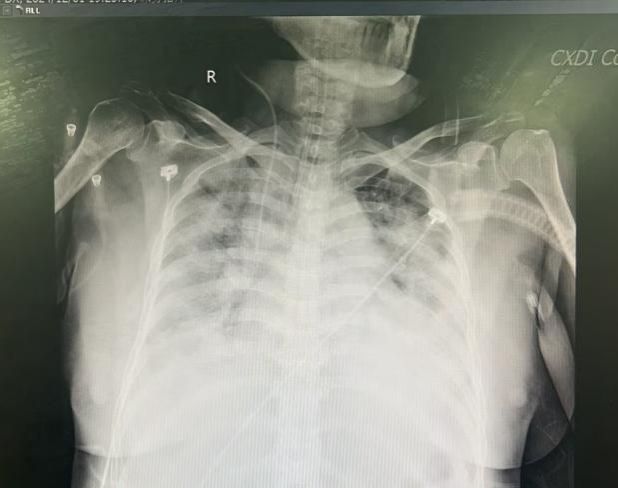

在接下来的治疗中,多学科团队紧密协作,制定个体化治疗方案。在给予抗病毒药物积极治疗甲型流感病毒肺炎同时,对患者进行全面的生命支持和并发症的预防和处理。经过11天的艰苦努力,患者肺功能逐步恢复,胸片肺部阴影明显吸收,各项检验指标趋于正常,成功撤离ECMO,康复治疗10余天后顺利出院。

ECMO上机前 ECMO撤机后